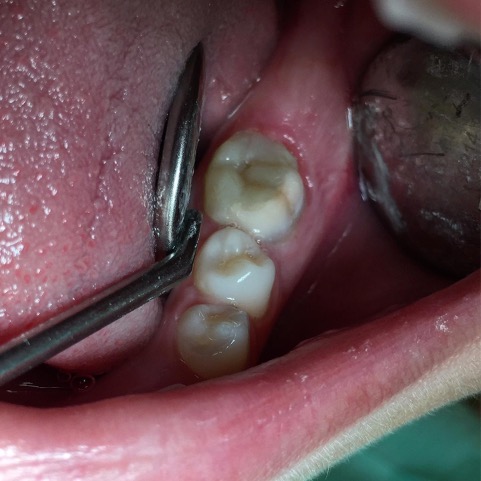

Un trattamento endodontico consiste nel salvare un dente compromesso da carie, traumi o fratture rimuovendone polpa e nervi infetti/infiammati responsabili di dolore, ascessi, cisti e granulomi.

Un adeguata endondonzia serve per salvare quei denti che altrimenti sarebbero destinati ad essere estratti. Quando un dente viene devitalizzato viene privato della sua irrorazione sanguigna e del nutrimento, rendendo la sua struttura più “vetrosa” quindi più fragile e soggetta a fratture. Per questo motivo è consigliabile nella maggior parte dei casi capsulare i denti una volta che hanno perso la loro vitalità.